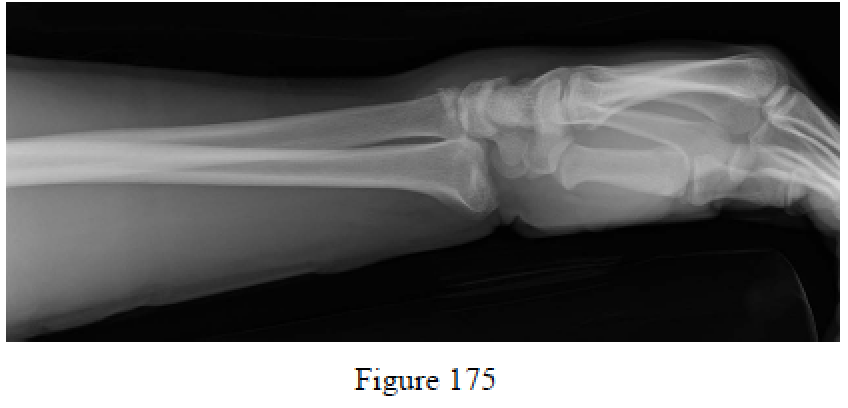

Ilyas AM, Mudgal CS. Radiocarpal fracture-dislocations. J Am Acad Orthop Surg. 2008 Nov;16(11):647- 55. Review. PubMed PMID: 18978287.

Mudgal CS, Psenica J, Jupiter JB. Radiocarpal fracture-dislocation. J Hand Surg Br. 1999 Feb;24(1):92-8. PubMed PMID: 10190615.